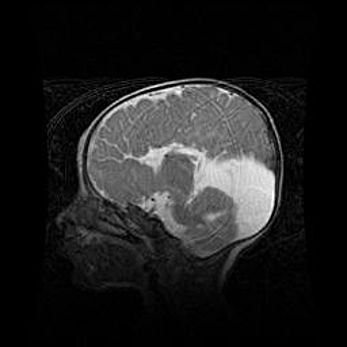

Множественные кисты обоих полушарий головного мозга, наибольшая из них в правой затылочной области. Ассиметричная атрофическая гидроцефалия.

Возраст: 7 месяцев

Вес: 5660 г

Пол: мужской

Окружность головы: 41,5 см

Срок гестации: 28-29 недель

Кисты головного мозга развиваются в результате многоочаговых некрозов вещества мозга и возникают вследствие перенесенной перинатальной инфекции, менингитов, энцефалитов, асфиксии, родовой травмы, расстройств мозгового кровообращения различного генеза. Образованию кист в веществе головного мозга плодов и новорожденных способствуют такие факторы, как высокое содержание в нем воды, недостаточная (или отсутствие) миелинизация и слабая астроглиальная реакция на повреждение.

Кисты могут сочетаться с гидроцефалией и другими поражениями головного мозга.